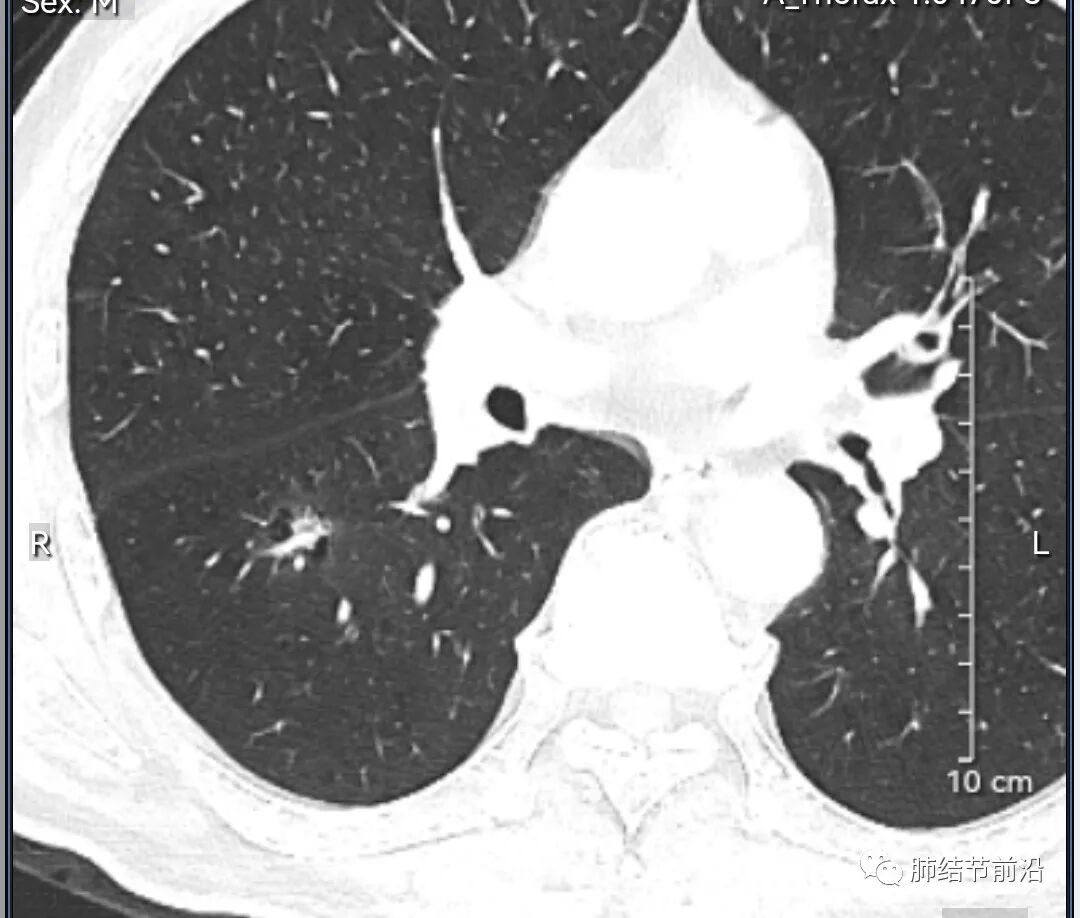

男性,67岁,重度吸烟史。CT发现右下肺囊腔。来看一下这个CT的特点:

该囊腔形态非常有特点,和常见的圆形肺大泡有很大的区别。

1.囊腔中央实性成分,周围有磨玻璃影。

2.囊腔中央有血管。

3.囊腔外周有分叶形态。

4.囊腔有胸膜牵拉。

出现这几种形态,CT可以确认恶性的腺癌。这个囊腔形成的机制,为肿瘤实性成分堵塞细支气管形成活瓣,肺泡内压力增高破裂行成,因此肺内血管成分保留。由于肺泡压力增高,而呈分叶状。另外,也有肿瘤的胸膜牵拉这一特点。

囊腔周围磨玻璃+囊腔中央血管为特征性表现。如果持续存在,几乎可以100%确认为早期肺腺癌。